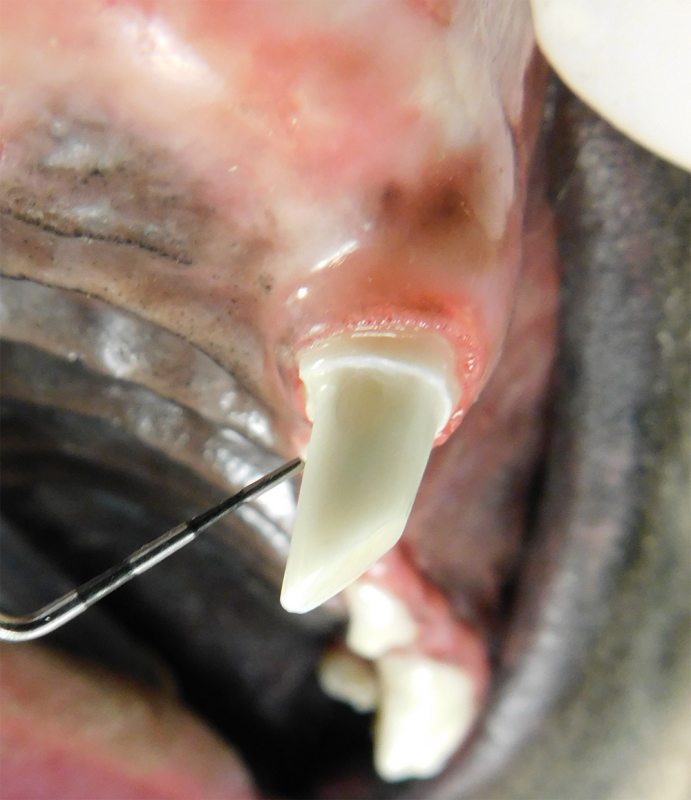

Vital Pulp Therapy

Young dogs less than 1 year of age that have very recently (less than 48 hours) fractured a tooth may be a candidate for vital pulp therapy. This procedure keeps the tooth alive and is very minimally invasive. For best results, this procedure should be performed within 48 hours of the tooth fracture. If your pet is not a candidate for this procedure, root canal therapy can still be performed to preserve the structure and function of the tooth. Vital pulp therapy can also be used to treat malocclusions.